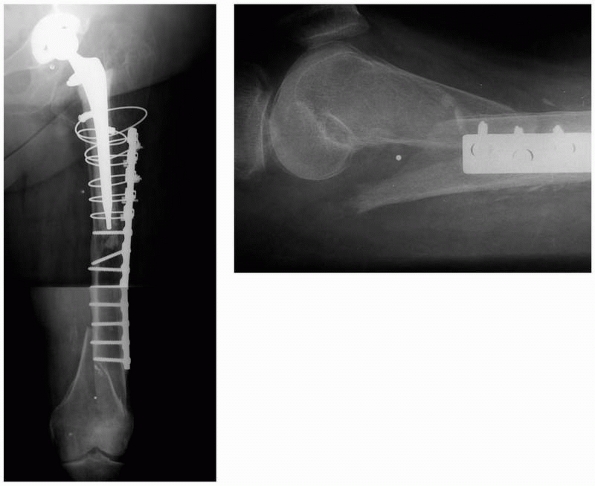

![]() |

|

FIGURE 21-10 Proximal femoral allograft/revision stem composite for treatment of Vancouver type B3 periprosthetic femur fractures. A. The allograft/prosthesis composite is inserted into the native host distal femoral segment. B.

Any remaining proximal sleeves of host bone with soft tissue attachments are secured to the allograft and across the allografthost junction. C. The greater trochanter is separately attached to the allograft. |

FIGURE 21-11 A.

Ill-advised treatment of a Vancouver type C femur fracture distal to a hip arthroplasty stem. The nail eroded through the anterior cortex and the fracture developed nonunion. This was treated with nail removal, ORIF with a lateral plate, autologus bone graft to stimulate nonunion healing, and an anterior strut graft to restore bone stock (B,C). |